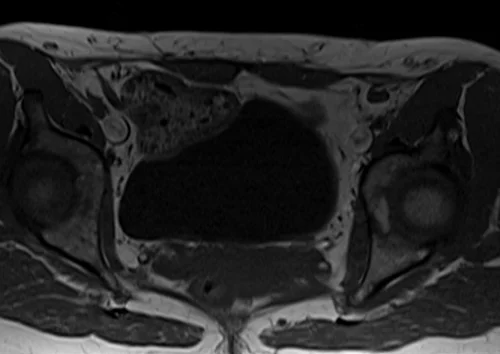

L plexus mri T1 axial images